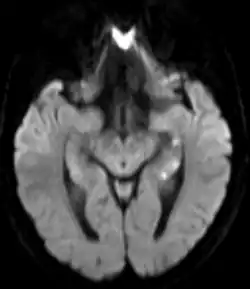

| Areas of hypoperfusion, seen above in the left sided hippocampus (seen as white punctate lesions on diffusion weighted MRI) are a characteristic finding in Transient Global Amnesia | |

There is no universally accepted diagnostic criteria for TGA, however proposed diagnostic criteria include: the absence of seizures, the absence of a head injury, symptoms that resolve within 24 hours, and the dysfunction or impairment being limited to amnesia (both retrograde and anterograde).[4] TGA is a clinical diagnosis and brain imaging or other testing is not required for the diagnosis.[4] However, brain imaging is often obtained to rule out other serious causes of sudden amnesia, including a stroke. Brain imaging is usually normal during and immediately after an episode of TGA. However delayed diffusion weighted MRI (obtained 12–48 hours after the episode) can sometimes show punctate lesions in the hippocampus (one of the areas of the brain responsible for memory) or adjacent areas of the brain. These lesions are transient; often persisting for several days after the episode.[4]

Functional MRI may show bitemporal hypoperfusion during an episode of TGA. Other areas affected include the hippocampus, parahippocampal gyrus, and amygdala.[4]